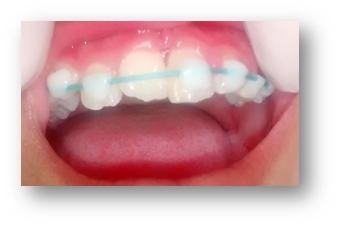

PRESENTACIÓN DEL CASO

Paciente masculino 9 años llega a consulta con dolor espontáneo en la arcada inferior izquierda, en la exploración extraoral presentaba asimetría facial. A la exploración intraoral se observó caries en la pieza 3.4 y aumento de volumen en la zona periapical. Al hacer pruebas de sensibilidad respondió positivo a la percusión, palpación y negativo al frío. Radiográficamente se observó una lesión periapical y la incompleta formación de la raíz de la pieza 3.4 además de ensanchamiento del ligamento periodontal.

Diagnóstico: Necrosis Pulpar y Periodontitis Apical Aguda.

Tratamiento: En la primera cita se trabajó sin anestesia, se aisló y se eliminó caries, se tomó cavometría hasta donde sentía sensibilidad, irrigando con hipoclorito de sodio 5.25% se colocó pasta triple antibiótica (metronidazol, minociclina y ciprofloxacina) y se colocó Cavit, en la siguiente cita regresó asintomático y se eliminó la pasta, se indujo sangrado inundando el conducto y se colocó un tapón de MTA.